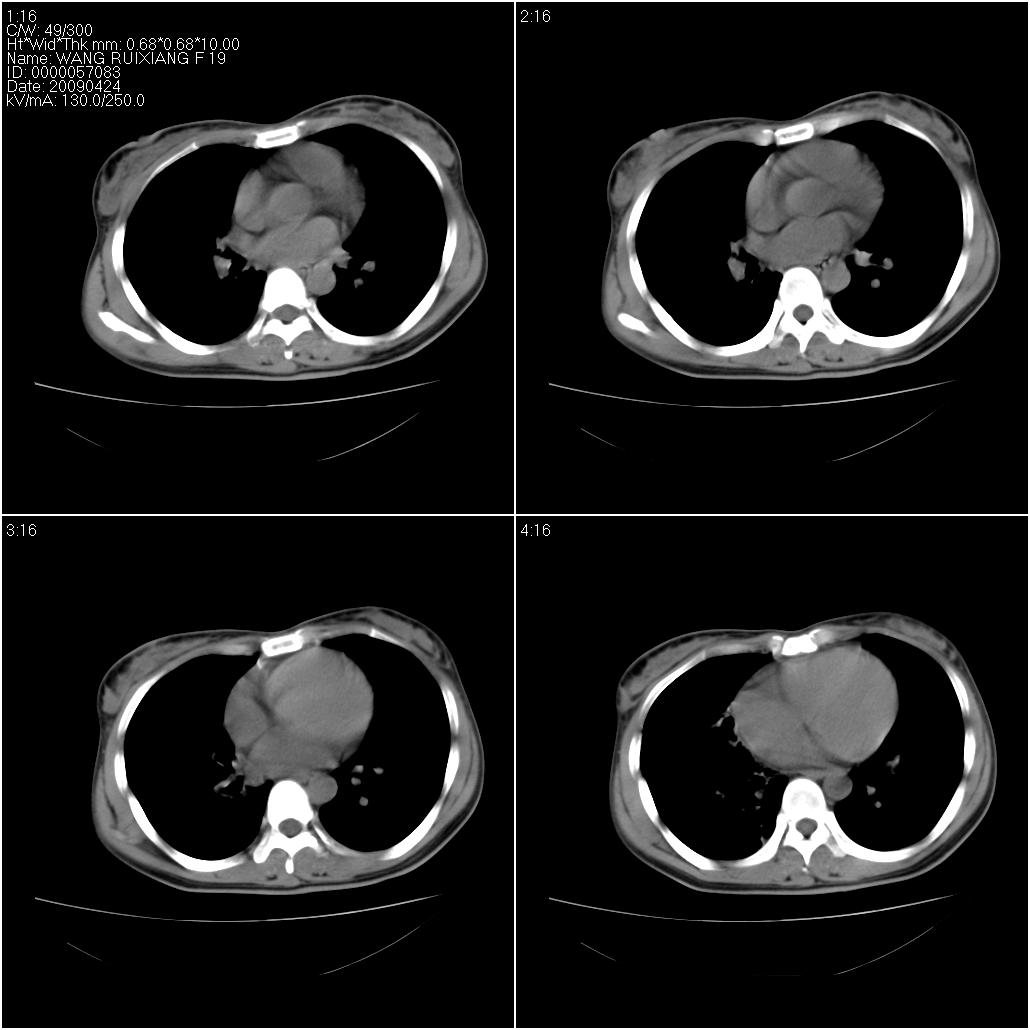

标题: CT19588:女性,39岁。患者胸闷不适,上楼时气喘。 [打印本页]

标题: CT19588:女性,39岁。患者胸闷不适,上楼时气喘。

片子上的年龄为19岁,是操作错误。该患者于去年5月份曾做平片和ct扫描,和这一次的ct检查没有明显变化。当时诊断为肺结核,进行抗痨治疗至今,但没有改善。呼吸功能试验为混合型呼吸困难。除此之外,该患者没有其他方面没有的临床症状和体征

两肺见斑点片状阴影,部分病灶密度较高,右下肺见小囊状及柱状蜂窝状阴形,考虑为两肺结核以阵旧性为主,右下肺支扩。

1)两肺继发性肺结核(以增殖病灶为主)。2)两肺下叶支气管扩张。

1)两肺继发性肺结核(以增殖病灶为主)。

2)两肺下叶支气管扩张。